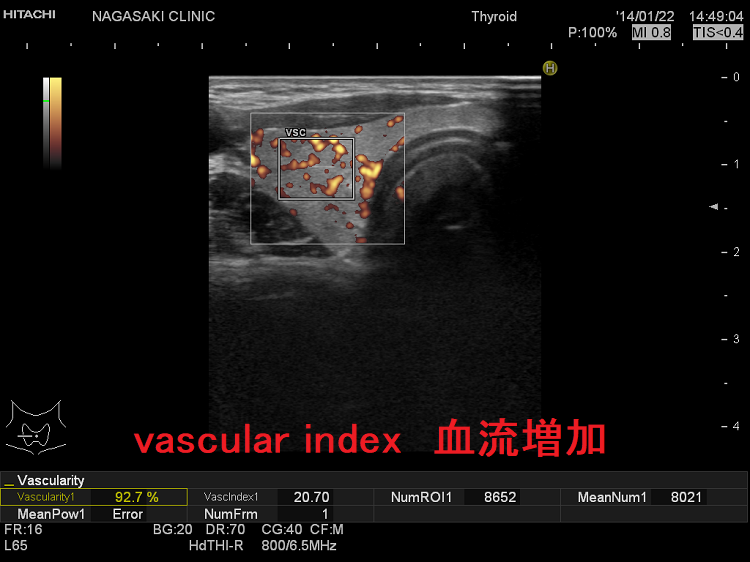

甲状腺内の血流評価 [%vascuralityまたはvascular index(血流指数)または血管密度]

甲状腺内の血流を定量評価[%vascuralityまたはvascular index(血流指数)または血管密度]

現在、vascular index(血流指数)の有用性を検証中です。甲状腺機能亢進症/バセドウ病甲状腺機能低下症無痛性甲状腺炎の回復期でも甲状腺内血流は増加し、少なくとも甲状腺ホルモンが正常範囲を外れているのを瞬時に予測できます。

vascular index 血流増加

甲状腺機能亢進症/バセドウ病では、著明な血管増殖のため甲状腺内の血流が増加します。

甲状腺機能亢進症/バセドウ病の血流増加